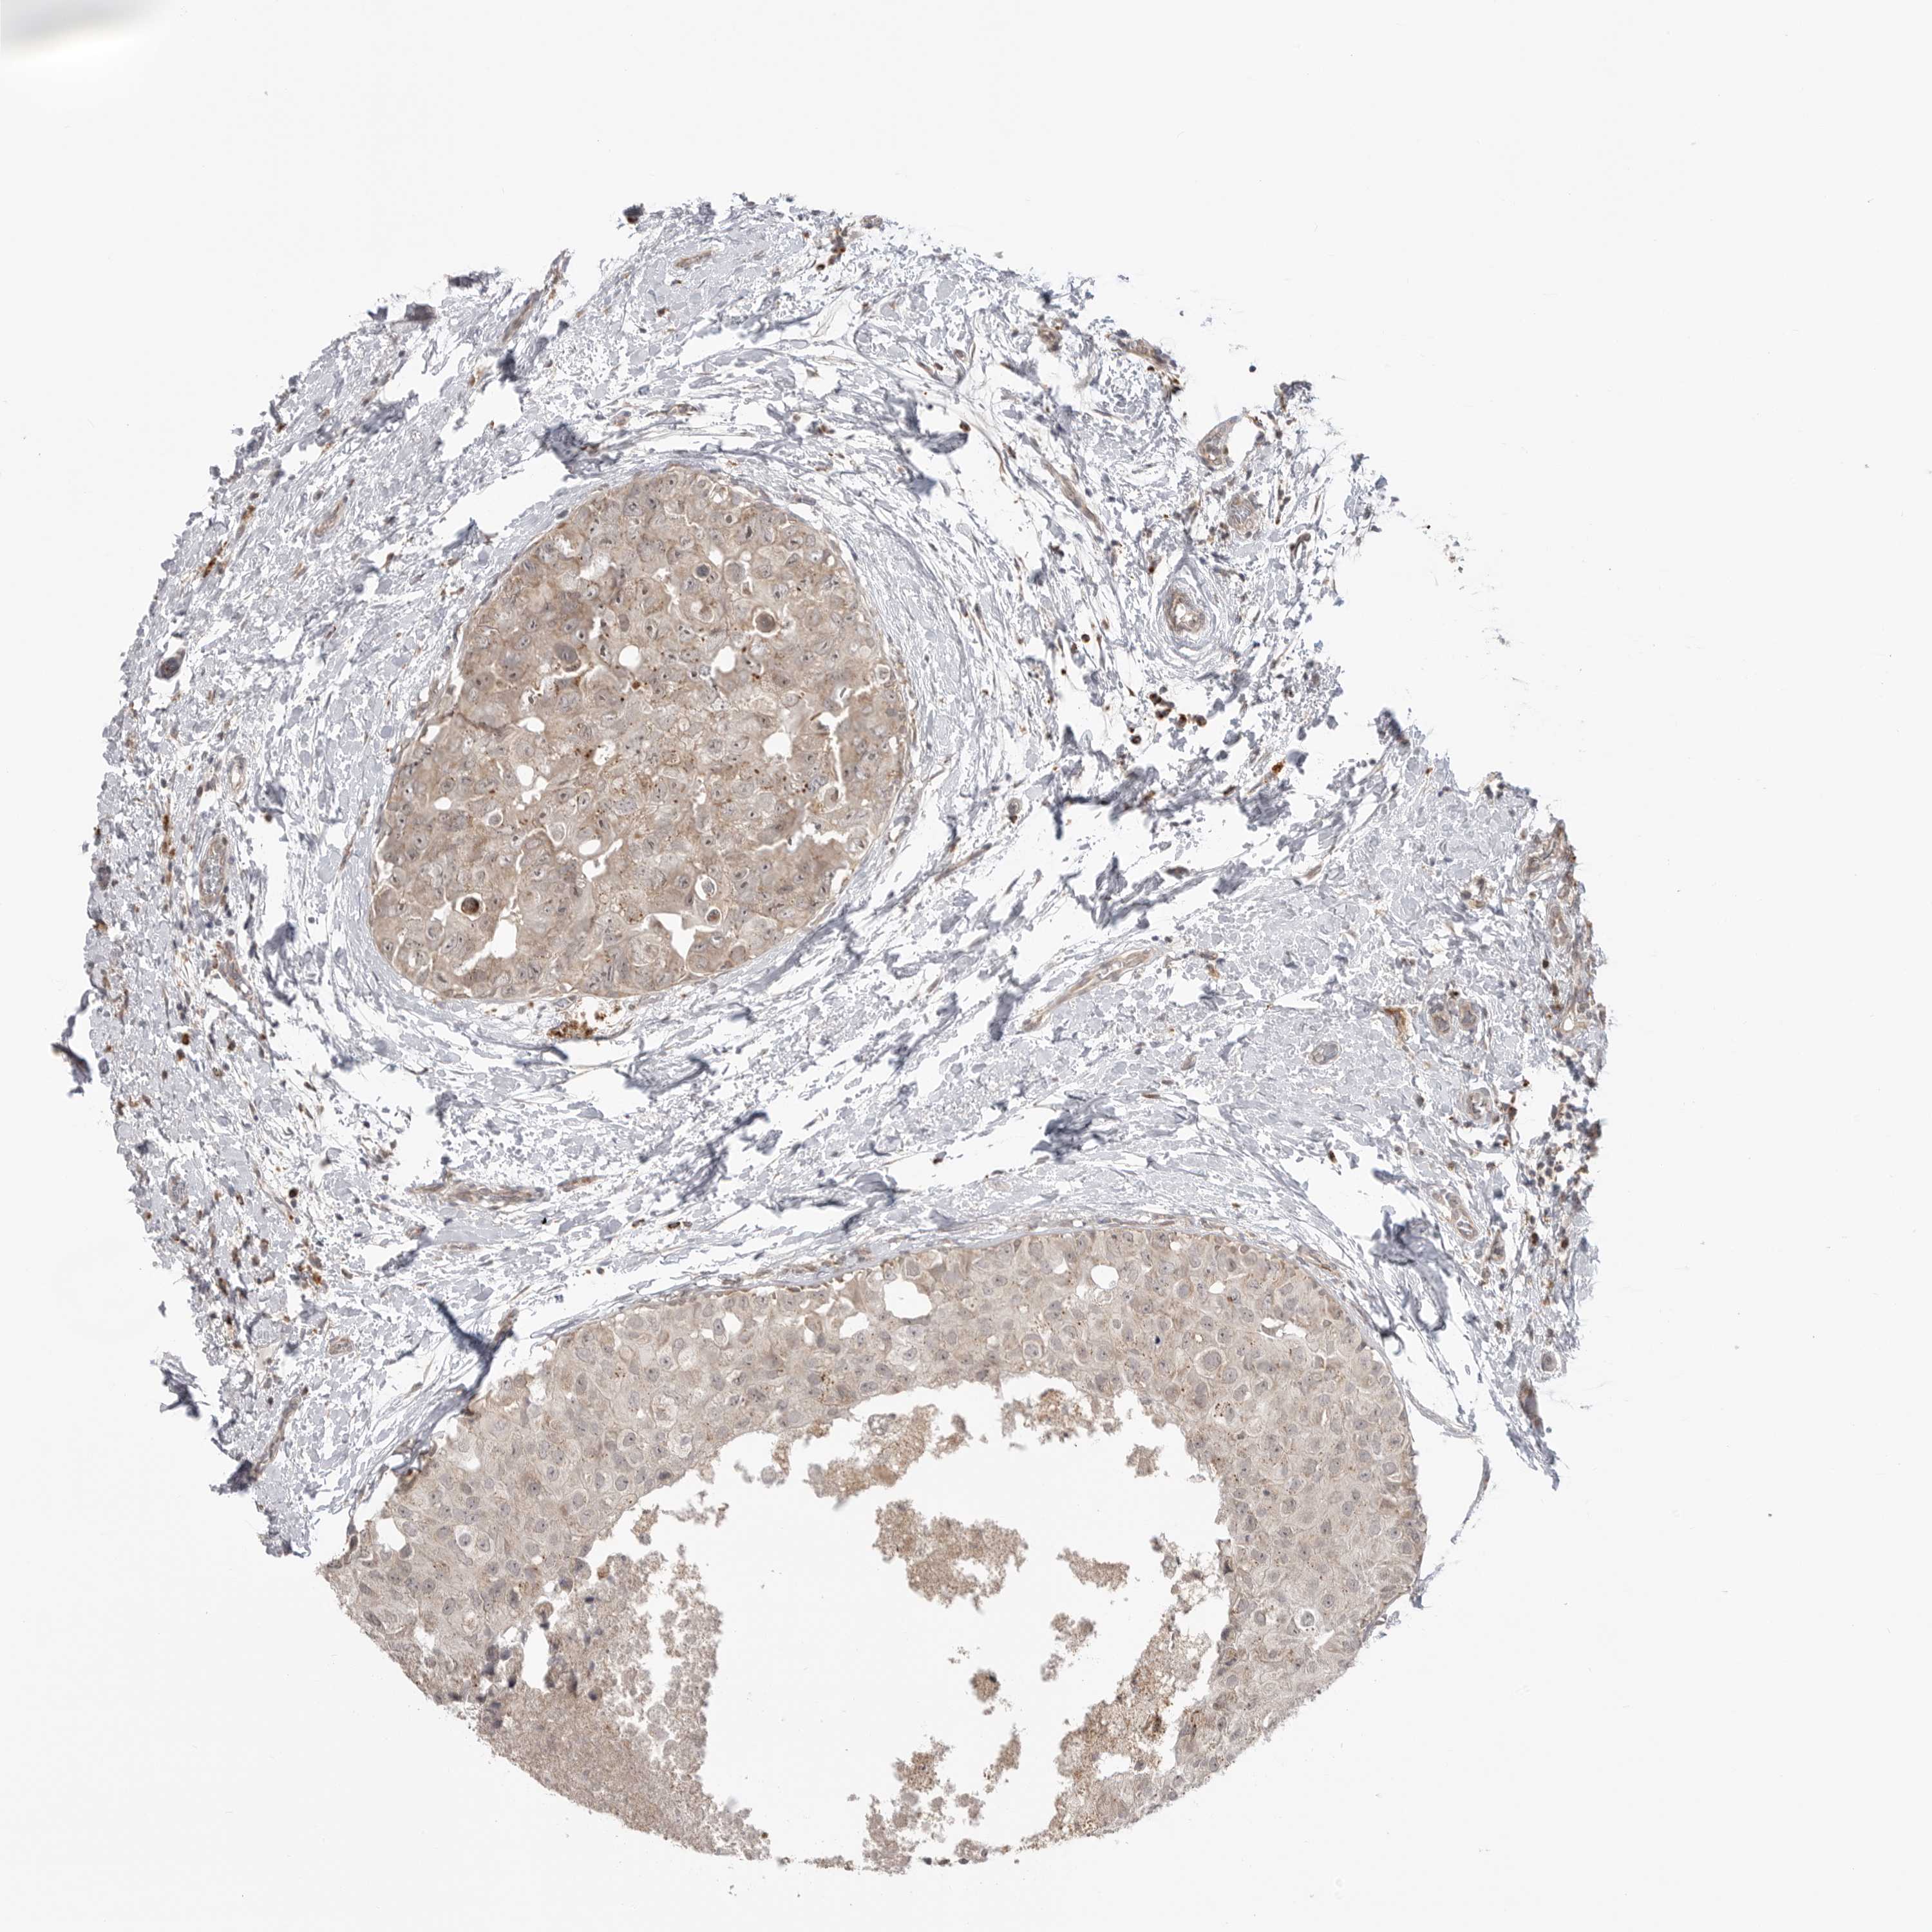

BRCA TCGA BRCA VALIDATION PROTEIN EXPRESSION